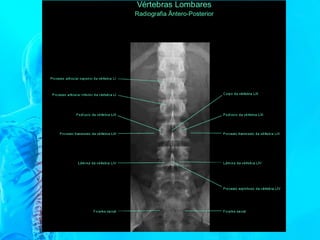

VÉRTEBRA

LOMBAR

Apresenta um

processo transverso

bem desenvolvido

chamado apêndice

costiforme. Pode ser

diferenciado também

por não apresentar

forame no processo

transverso e nem a

fóvea costal.

VÉRTEBRA LOMBAR

COLUNA LOMBAR

C. LOMBAR